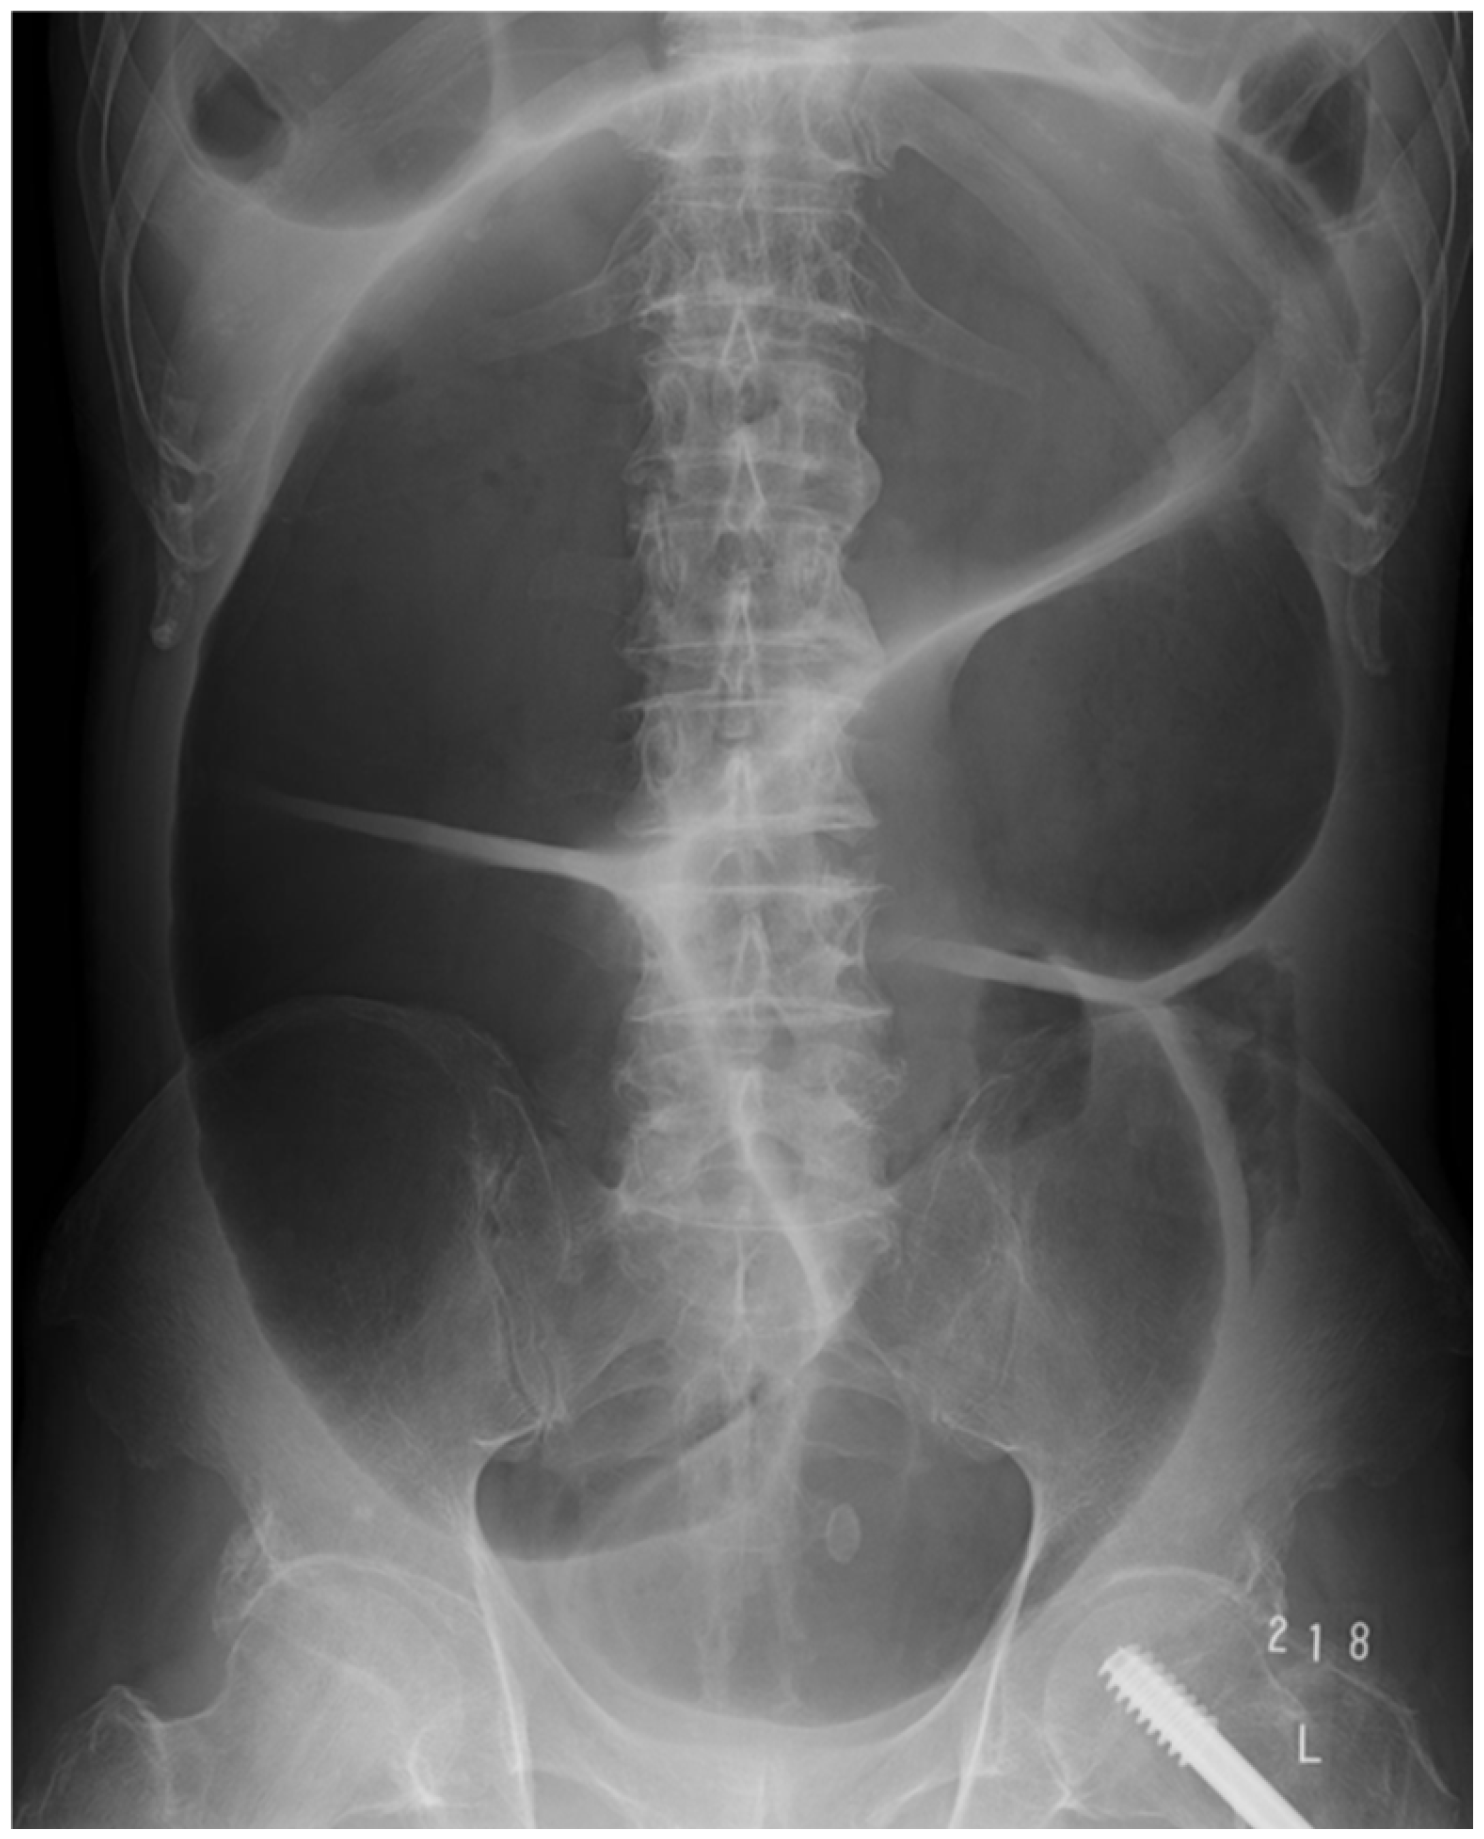

The diagnosis of this condition is not difficult when utilizing imaging techniques. A distended colon without a mechanical obstruction is visible on abdominal X-rays and CT scans. An illustrative abdominal X-ray from a case is presented in Figure 2. The case in question pertains to a 66-year-old female patient diagnosed with schizophrenia, who presented with acute abdominal distension. The patient had undergone osteosynthesis for a left femoral neck fracture several years prior and had been receiving 300 mg of clozapine for the treatment of schizophrenia. It is noteworthy that the patient had been experiencing chronic constipation. At the time of the onset of Ogilvie’s syndrome, the patient exhibited mild abdominal discomfort and was not vomiting. However, the patient subsequently developed sepsis due to the bacterial translocation caused by colonic distension. Blood cultures revealed the presence of Escherichia coli, leading to a further deterioration in the patient’s overall condition. The administration of psychotropic medications was suspended, and the patient was treated with decompression via a nasogastric tube and the infusion of meropenem. Following approximately 20 days of treatment, the patient demonstrated sufficient recovery to resume oral alimentation.

Figure 2. The photograph of this case shows the marked dilation of the large intestine that is typical of Ogilvie’s syndrome.